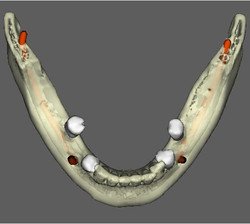

CIRURGIA GUIADA

REFORMATAÇÃO COM DENTALSLICE

Para trabalhar no DentalSlice basta solicitar na Clinica Serraro a tomografia computadorizada, onde as imagens DICOM (arquivos da tomografia) serão convertidas para o ambiente DentalSlice criando um arquivo que será enviado para o cirurgião dentista.

O Dental Slice é uma ferramenta de planejamento implantodôntico pré-operatório, desenhado para oferecer auxílio cirúrgico-protético com alto nível de precisão e aumentar a margem de segurança no tratamento.

O programa é acessível a qualquer cirurgião dentista e permite que o planejamento seja realizado pela própria equipe que vai realizar a cirurgia. As imagens também podem ser segmentadas, oferecendo melhor visualização de detalhes, como por exemplo do seio maxilar, canal da mandíbula ou de lesões.

• Tipos de Conversões do DentalSlice

O Dentalslice pode ser solicitado na Clinica Serraro de várias formas:

Limpeza de artefatos